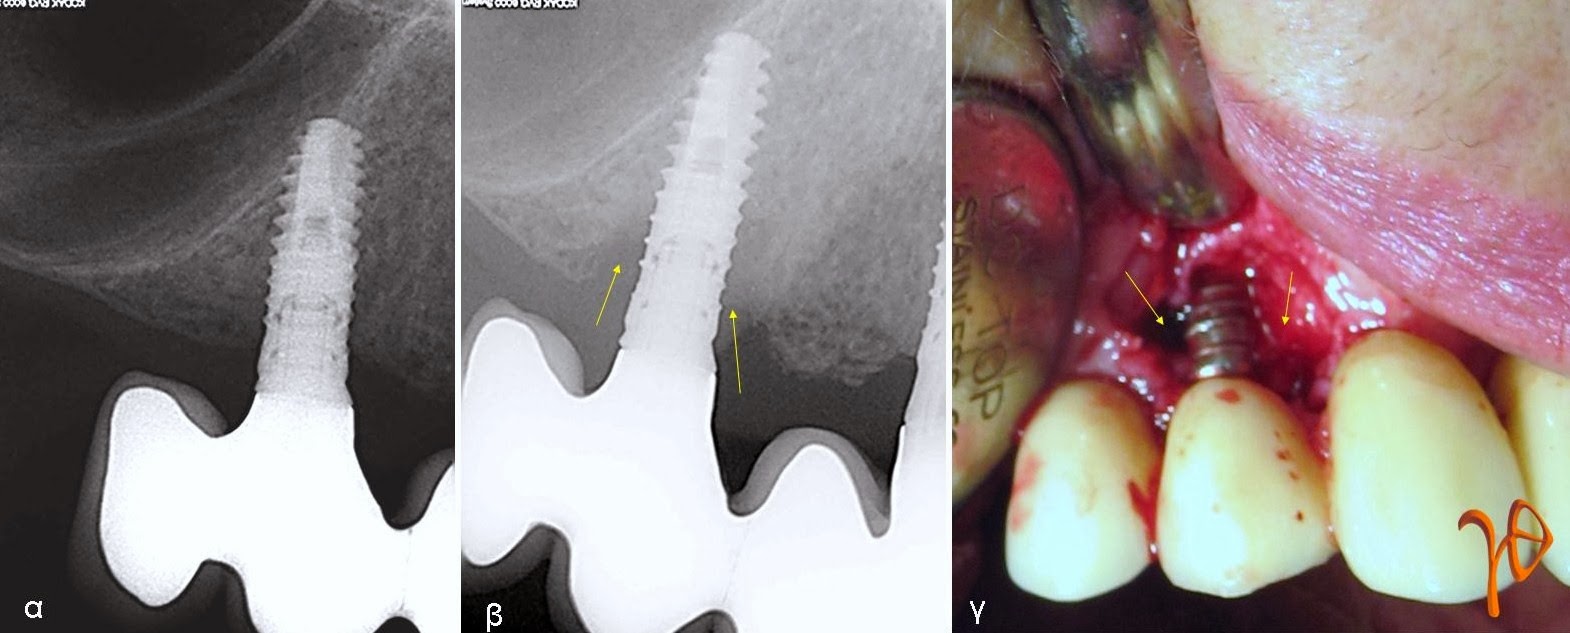

Μια σχετική περίπτωση απεικονίζεται στην παρακάτω φωτογραφία, όπου παρατηρούμε την εξέλιξη της νόσου στο οδοντικό εμφύτευμα #14 που στηρίζει πρόβολο #15 σε συγκολλούμενη ακίνητη προσθετική εργασία. Το μόνο σύμπτωμα του ασθενή ήταν η αίσθηση πόνου κατά την ψηλάφηση της παρειακής επιφάνειας του βλεννογόνου αντίστοιχα με το εμφύτευμα. Η κλινική εξέταση έδειξε παρειακό αιμορραγικό θύλακα βάθους 7mm και άπω υπερώιο βάθους 6mm. Ακτινογραφικά υπήρχε γωνιώδης οστεολυσία κυρίως άπω, αλλά και εγγύς του εμφυτεύματος.

Εικόνα: (α) Η περιοχή κατά την αρχική φόρτιση, (β) Μετά από 5 χρόνια με οστεολυσία (βέλη), (γ) Χειρουργική προσπέλαση που δείχνει το μέγεθος της οστικής απώλειας(βέλη)>/

Η χειρουργική αποκάλυψη της βλάβης επιβεβαίωσε τα κλινικά και ακτινολογικά ευρήματα. Η μεγαλύτερη οστική απώλεια εντοπιζόταν άπω του εμφυτεύματος. Η περιοχή καθαρίστηκε από τους μαλακούς ιστούς, εκπλύθηκε με χλωρεξιδίνη και φυσιολογικό ορό και συμπληρώθηκε με αλλοπλαστικό υλικό και απορροφήσιμη μεμβράνη.